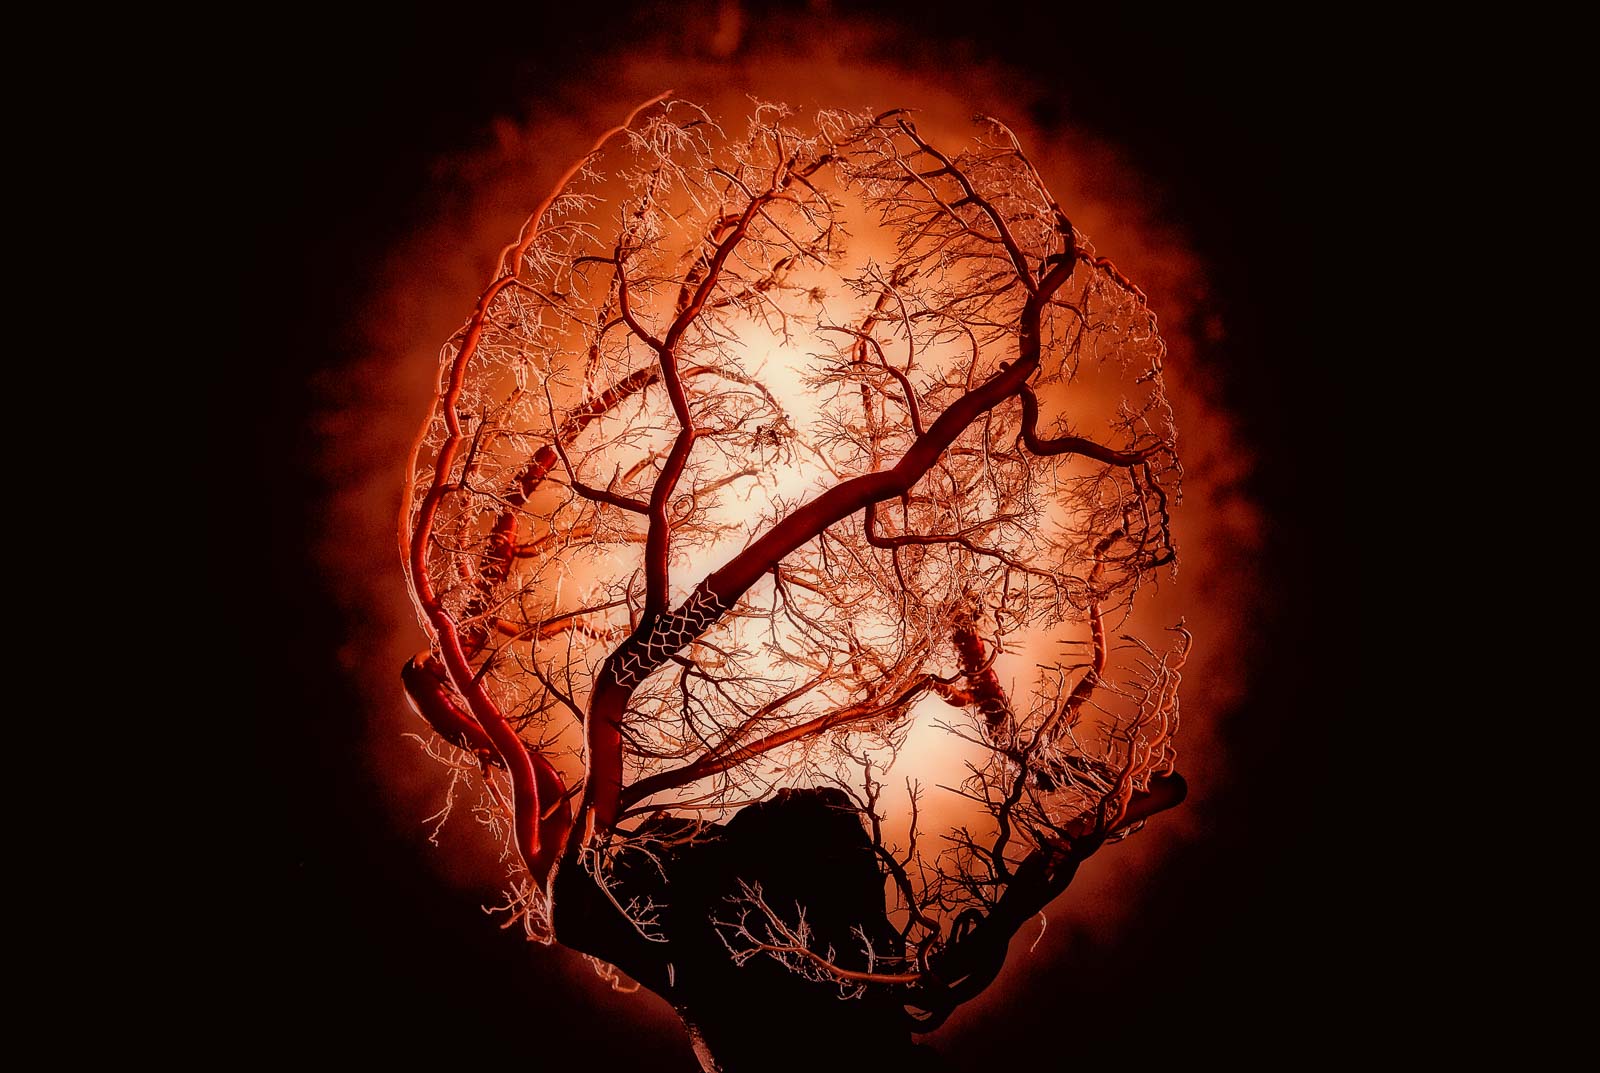

out of the blue design is a consultancy focused on solving complex global problems. For more than twenty years, we have worked with medical device, biotechnology, healthcare, and data analytics companies. Our powerful integrated brands utilize award-winning, key images to tell stories and simulate everything from the inside of a heart to the workings of a continuous diabetes monitor.